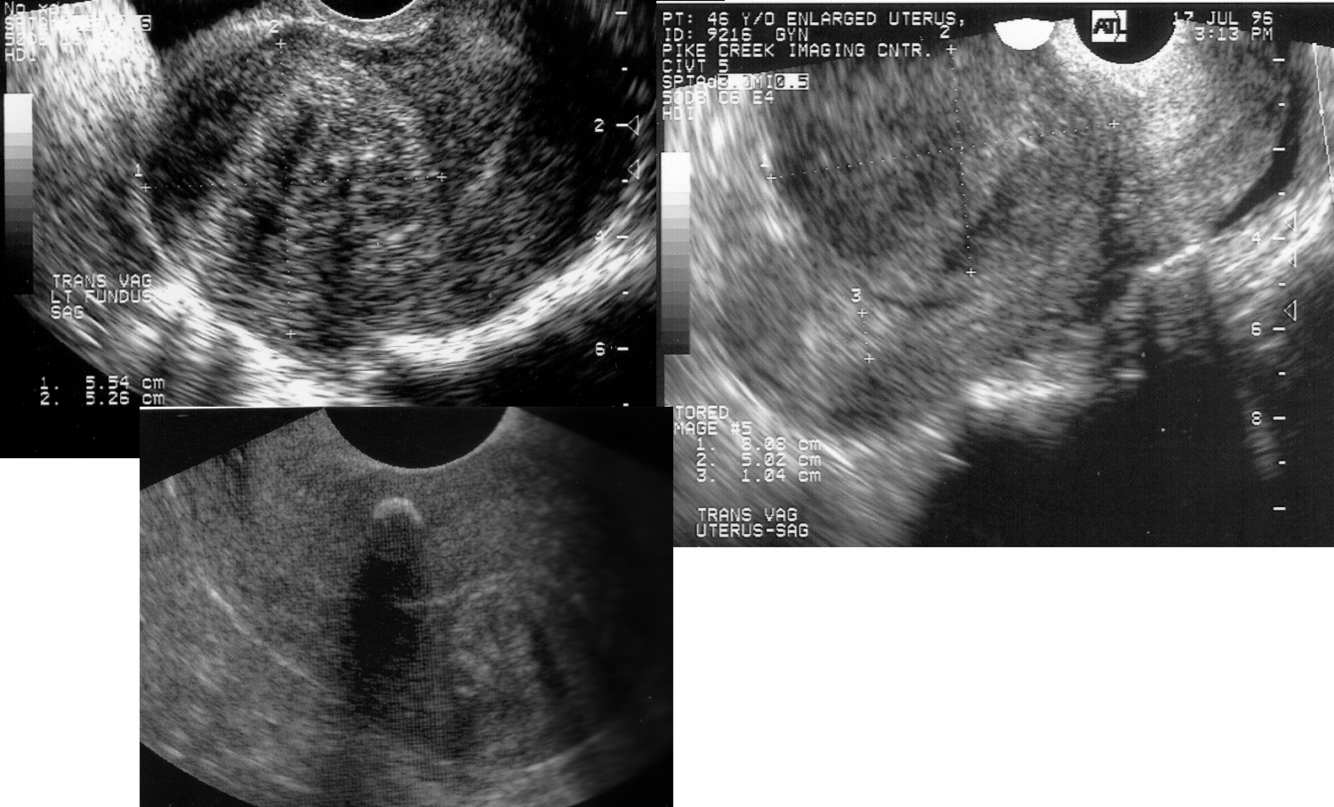

Uterus w/ Fibroids

*

submucosal fibroids